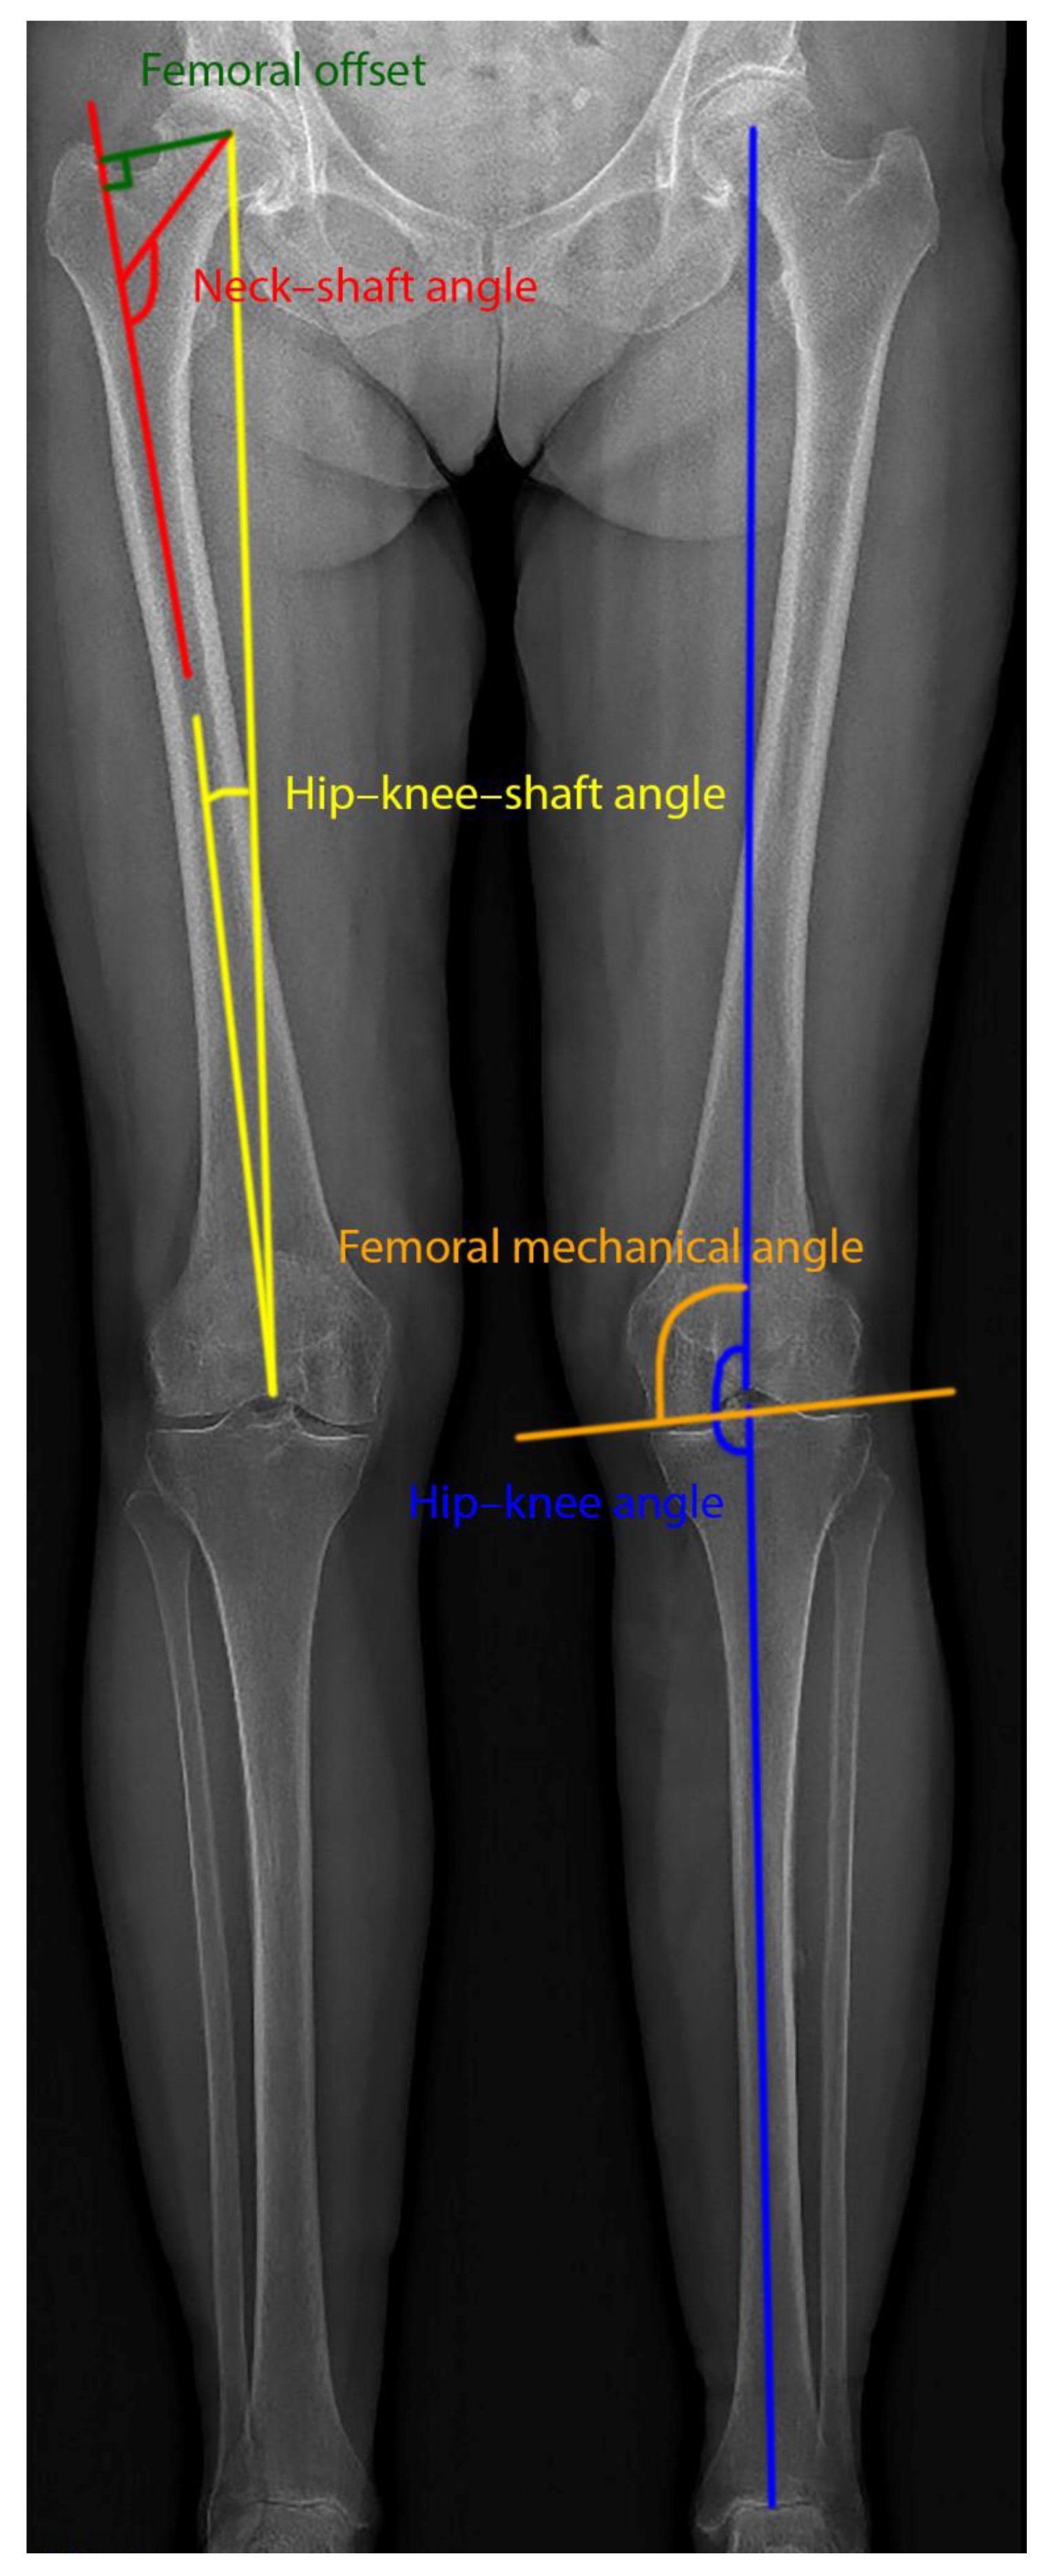

Preoperatively, biplane radiographic images were captured in a standing position with the EOS® system (EOS imaging, SA, Paris, France) for all patients [11,12]. An accurate 3D model of the lower extremities was reconstructed for each patient from the lateral and anterior images, as described and validated in previous studies [25]. The 3D model was made using sterEOS® (EOS imaging, SA, Paris, France) and was then used for planning the prosthesis (hipEOS®, EOS imaging, SA, Paris, France). From the 3D reconstruction, five clinical leg parameters, which were described in detail elsewhere [25,26], were considered to assess the leg alignment (Figure 1).

Figure 1.

Clinical leg parameters overlaid on the frontal EOS image.

- Hip–knee–shaft angle (HKS): This was measured on the frontal plane, considering the femoral mechanical axis (which connects the centers of the femoral head and the trochlea) and the femoral anatomical axis (axis from the center of the trochlea to the center of the distal diaphysis of the femur).

- Femoral offset (FO): The distance defined by the center of the femoral head and the orthogonal projection of this point on the femoral anatomical axis.

- Neck–shaft angle (NSA): The angle measured between the axis going from the center of the femoral head through the femoral neck and the line drawn down the center of the femur’s diaphysis.

- Hip–knee angle (HKA): The angle in the frontal femoral plane between the mechanical axes of the femur and the tibia (the line from the center of the tibial plateau to the center of the distal articular surface of the tibia). Valgus > 180°, varus < 180°.

- Femoral mechanical angle (FMA): The angle that is defined in the frontal plane between the femoral mechanical axis and the line through the medial and lateral condyles (the two most distal points).